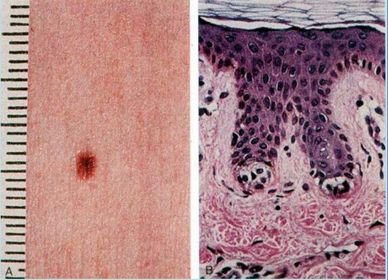

Diagnóstico NEVO

Diagnóstico Completo NEVO JUNCIONAL

Diagnóstico Completo NEVO INTRADÉRMICO

Diagnóstico e Características MELANOMA Melanócitos atípicos, núcleo grande, nucléolo evidente.